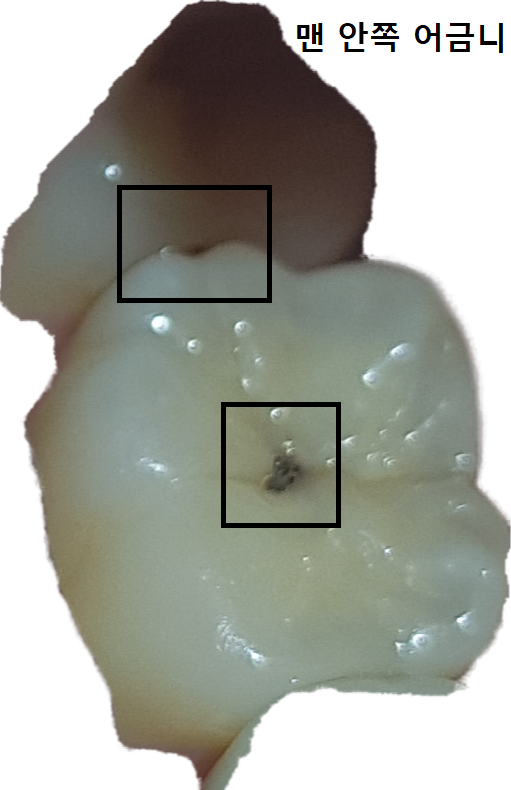

이런 충치는 어떻게 치료 하나요 보통?

충치 때우면 될 줄 알았는데 인접면에도 있다고 인레이로 치료하겠다고 하시더라구요. 인레이 중에 옆치아에도 충치가 발견되면 때울수도 있다고 하시는데 일단 이게 제가 사진상으로 찍을 수 있는 최대인데 레진으로 치료하기는 힘들까요? 그냥 인레이 하는 게 낫나요?

윗치아가 맨 안쪽 어금니입니다.

• 사진으로만 봤을 경우에는 교합면에 충치가 있는 것으로 보입니다. 교합 면에만 충치가 있다 하면 레진으로 간단하게 치료를 할 수 있습니다. 하지만 인접면까지 충치가 있다면 인레이나 크라운 치료를 하는 것이 좋을 수 있습니다. 자세한 확인을 위해서 치과에서 진료를 받아보는 것을 권해드립니다

• 사진상 보이기로 씹는면(교합면) 충치가 있는 것은 맞고 이건 깊지 않다면 단순히 레진으로 떼웁니다 다만 문제는 옆면 충치입니다 옆면 충치는 레진으하기 어려운 경우도 많고 그리고 치아2개가 같이 영향을 받을수도 있으며 옆면은 법랑질이 얇아 금방 신경이 영향을 받기도 합니다